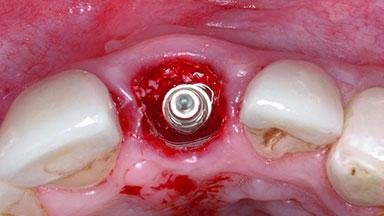

Replacement of a Failing Upper Left Central Incisor: Immediate Placement of an RC Bone Level Implant and Provisionalization

Type of Implants Two-Piece

Bone Augmentation Horizontal|Simultaneous

Soft Tissue Grafting Simultaneous

Placement Protocol Immediate implant placement

Socket Integrity Damage to one or more bone walls

Bone Volume Damage to one or more socket walls